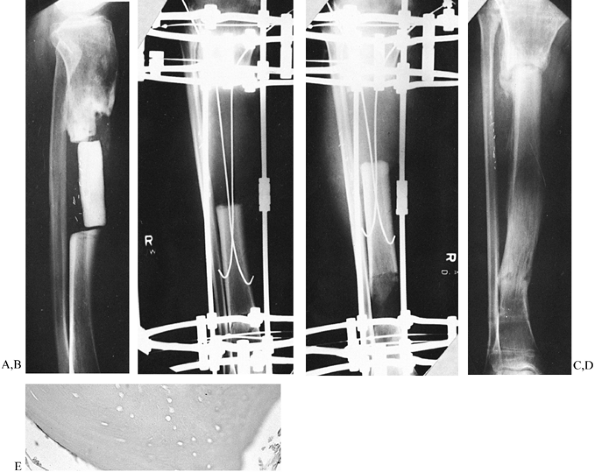

Figure 32.43. A:

Bilateral genu varum from varus deformities of both femurs and the right tibia. Both tibias have been previously operated on. The right tibia still has a varus deformity. The preoperative planning of the right side of this deformity was illustrated in Figure 32.23. B: A single level of osteotomy was chosen for both the tibia and the femur. One could justify two levels of osteotomy within each bone; however, since the amount of bowing in each bone was not severe, it was felt that this could be treated as a single apex angular deformity, recognizing that it truly was a multiapex angular deformity. Therefore, we chose to ignore the anatomic axis of the tibia and realign both the mechanical axis of the tibia and the joint orientation of the knee and ankle. This gives the patient a result similar to that achieved on the plated left side. The alternative would have been a combined proximal and distal tibial osteotomy, which would normalize both the anatomic and the mechanical axes of the tibia. An acute correction was performed in the femur at a level distal to the apex of the deformity, as described in Figure 32.23, to minimize the lateral indentation of the side that would result from a single-level, more proximal osteotomy at the apex. C: The result demonstrates complete realignment of the hip, knee, and ankle joint orientations, as well as the mechanical axis. On the opposite side, the osteotomy was performed slightly distal to the apex of the deformity and, therefore, a lesser amount of translation was needed. The result in terms of joint alignment and orientation is identical. |

The clue that there is more than one apex of angulation is that the

single center of rotation determined by the intersection of the

proximal and distal mechanical axis lines is at a level where there is

no “obvious” angulation (Fig. 32.44, step 1).

In multiapical deformities, there is usually one obvious (diaphyseal,

hip, or ankle) apex and one less obvious angulation apex. The obvious

apex should be corrected first. The apex of this level may be chosen

based on cortical or midbone lines, or, in the case of hip or ankle

deformities, we know the apex is at the center of the joint. Once the

first apex of angulation is corrected, it will point to the second apex.

malalignment, correct it together with the tibial or femoral varus

angulation. With conventional techniques, the head of the fibula can be

osteotomized and moved distally. By the Ilizarov method, the proximal

fibula is pulled down to tighten (even overtighten) the lateral complex

(Fig. 32.15, Fig. 32.41).

The medial collateral ligament can also be tightened by distracting the

tibia through an osteotomy proximal to the insertion of the medial

collateral ligament. To tighten the medial collateral ligament without

pulling down the patellar tendon, direct the osteotomy of the tibia

obliquely, distally, and laterally, to exit below the tibial tuberosity

(Fig. 32.15).

opening wedge, dome, closing wedge, or angular displacement

osteotomies. Both distraction and conventional methods use all of these

osteotomy types. With conventional osteotomy, the correction is

achieved acutely in the operating room; stability is achieved with

internal or external fixation. The closing wedge technique is preferred

because of the good bone-to-bone contact possible. Conventional opening

wedge methods usually require a bone graft and have a higher incidence

of nonunion. The dome osteotomy is a compromise between the opening and

closing wedge, avoiding the length loss of the closing wedge method and

offering some adjustability. The complications with these techniques

include nonunion, osteomyelitis, compartment syndrome, nerve injury,

and vascular injury (6). Accuracy

of correction is often a problem, especially with the closing wedge

technique. Even with meticulous planning, factors such as x-ray

magnification, rotated x-rays, measurement error, the thickness of the

saw blade, and the expertise of the surgeon all contribute to

inaccuracy with conventional methods (19). After the operation, there is no nonoperative way to adjust incomplete correction (15,17).

accurate. Since Ilizarov’s technique is percutaneous, there is little

risk of compartment syndrome, nerve injury, vessel injury, nonunion, or

osteomyelitis. The correction is performed either acutely for small

deformities or gradually for larger deformities (25).

Gradual distraction prevents nerve stretch injuries, as can occur in

the correction of a valgus tibial deformity. The distraction method is

as accurate as one can measure on a radiograph, perhaps the greatest

advantage of Ilizarov’s technique. Even after acute corrections,

adjustments can be made to fine-tune the correction until the exact

alignment of the limb is achieved.

correct as frontal or sagittal plane ones. More complex deformities,

including rotation, translation, and limb-length discrepancy, can all

be managed simultaneously. Multilevel and multibone corrections can be

done since there is little blood loss and the apparatus can be applied

to multiple levels and bones simultaneously. Lengthening can be

performed for small and large discrepancies, as needed, at one or more

levels. Associated problems of nonunion, contracture, and osteomyelitis

can be treated at the same time. The apparatus allows for unrestricted

weight bearing and personal hygiene; weight bearing is usually

restricted with internal fixation, and bathing is difficult if a

protective cast is used.

related to external fixation, including wearing a bulky apparatus for a

prolonged period, pin infections, muscle transfixion, loss of joint

range of motion, and pain. With proper application of the device, the

last three problems should be minimal. More recently, with the use of

half

pins instead of transfixion wires, these problems have been significantly reduced.

advantageous in treating complex deformities. Nevertheless, it still

offers many advantages even for simple deformities that have a good

conventional alternative, such as high tibial osteotomy. The decision

to use Ilizarov’s distraction method rather than a conventional

osteotomy and fixation depends on all of these factors, not the least

of which is the surgeon’s experience in the application of the

distraction osteotomy.

using hinges consists of two levels of fixation proximal and two levels

distal to the apex of the deformity (Fig. 32.45).

Each level of fixation is perpendicular to either the anatomic or the

mechanical axis of the bone fragment to which it is affixed. The hinge

connects the proximal and distal blocks of fixation, articulating

between them at the desired center of rotation for correcting the

angular deformity (23).

![]() |

|

Figure 32.45. A:

Center of rotation hinge apparatus. There are two levels of fixation in each bone segment on opposite sides of the osteotomy. The rings are applied perpendicular to their respective bone segment. The hinge lies perpendicular to the ring. In this example, the hinge is applied over the apex of the deformity, with the hinge rod overlying the medial convex cortex of the tibia. On the concave aspect, there is a distraction rod connected by two twisted plates and a suspending post. The post connection to the twisted plate allows for self-adjustment of the distraction rod angle to that of the ring. B: After the correction is completed, all the rings are parallel and the hinge rods are colinear. Notice the open-wedge correction of the tibia and fibula and the change in angle between the distraction rod and the ring. C: For a juxtaarticular deformity of the tibia, the apparatus employs a translation hinge. Notice that the hinge is located over the level of the tibial physis. This is proximal to the upper ring. Two levels of fixation were achieved in each bone segment on opposite sides of the osteotomy. D: At the end of the correction there is an angulation and translation of the bone segments at the level of the osteotomy. The rings are now parallel and the hinge rod is straight. Notice again the change in orientation of the distraction rod to the rings. |

the convex side, then distraction of the concavity will lead to an

opening wedge correction (Fig. 32.34, Fig. 32.46A).

If the hinge is placed at a distance from the convex side of the apex

of the deformity, then lengthening will occur together with correction

of angular deformity (Fig. 32.46B, Fig. 32.47). Placing the hinge on the concave side of the deformity will lead to compression of the bone ends with angular correction (Fig. 32.46C, Fig. 32.48).

If the hinge is placed either proximal or distal to the level of the

osteotomy, then translation of the bone ends will occur with angular

correction during distraction of the concavity (Fig. 32.46D, Fig. 32.49).

Figure 32.46. A:

Opening wedge hinge. The hinge is located at the level of the osteotomy overlying the convex cortex of the bone. Distraction of the concavity leads to an opening wedge correction without separation of the convex cortices of the bone. B: Distraction hinge. The hinge is located away from the convex cortex of the bone but still at the level of the osteotomy. Distraction of the concavity leads to simultaneous lengthening with angular correction. The regenerate has the appearance of a trapezoid, with a wider separation on the concave side than on the convex side. C: Compression hinge. If the hinge is located at the level of the osteotomy but on the concave side of the bone, distraction of the concavity will lead to compression of the bone ends. If the bone ends allow, this will produce a closing wedge type of correction. D: Translation hinge. If the hinge is located proximal or distal to the level of the osteotomy, distraction of the concavity will lead to translation of the bone ends. In this example, the hinge is located at the intersection point of the convex cortices of the two bones and, therefore, distraction of the concavity leads to correction of the angulation and translation of the bone ends. |

Figure 32.47. Application of distraction hinges for lengthening and correction of deformity. A:

A 5-year-old girl with bilateral genu varum and shortening due to meningococcemia septic emboli. She has skin grafts adherent to the bone and, therefore, distraction must be performed very gently. B: Standing radiographs show the deformities and the preoperative planning markings for the placement of olive wires. C: The apparatus has a hinge located lateral to the convex aspect of the osteotomy. To augment the stability of the fixation, the distal hinge has a threaded rod applied through the center of the anterior and posterior hinge point. This can be performed only with distraction hinges. D: Toward the end of the correction, notice the increased length achieved through the distraction hinges without lengthening on the hinge rods. All of the lengthening is performed by distraction of the concavity. Notice that this method is gentle on the skin and there were no skin problems. E: The final radiographs demonstrate 8 cm of lengthening of both tibias with realignment. Notice the bilateral triangular shaped tali. Both feet were plantigrade at the end of the correction. F: The final appearance of both legs at the end of the lengthening and correction of deformities. |